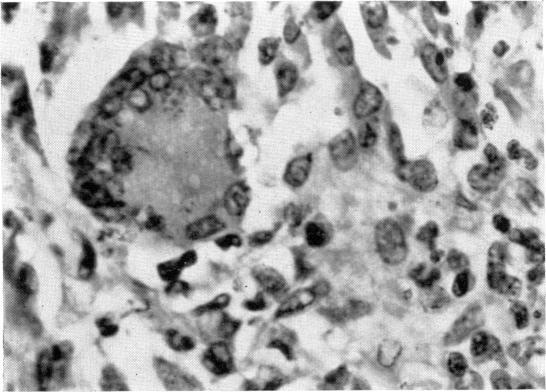

This paper describes the course of infection and development of immunity in guinea-pigs after intradermal inoculation of , and the use of and techniques to characterize the immunological response to infection and artificial immunization. Inoculation of 10 amastigotes into the ear produced a nodule which ulcerated in 2–3 weeks and healed in 8–16 weeks. 8% of animals developed cutaneous metastases which healed with the original lesions. Histology of the primary lesions showed epidermal necrosis overlying a mass of parasitized macrophages which, after 4–6 weeks, became surrounded and infiltrated by lymphocytes. Histological changes in the draining lymph node began after 3 days and proceeded for 6 weeks; both germinal centres and paracortical areas were hyperplastic and the medulla contained many plasma cells. Superinfection produced an `isophasic' lesion, but reinfection after healing elicited only a delayed hypersensitivity response. Artificial immunization with soluble and insoluble antigenic extracts of in Freund's complete adjuvant partially protected against infection; extracts of other leishmanial species failed to protect. Immunological paralysis, attempted with intravenous injections of soluble antigen, increased the severity of subsequent infection. Both infection and immunization were accompanied by delayed hypersensitivity which could be transferred passively by lymphoid cells. Cell-mediated immunity was studied by the ability of soluble leishmanial antigens to transform lymphocytes, to inhibit macrophage migration, and to induce the production of lymphokine factors from lymphocytes of sensitized animals. A target cell system was devised in which sensitized lymphocytes destroyed monolayers of parasitized macrophages. Cross reactivity of leishmanial with mycobacterial antigens was shown in skin tests and in target cell destruction, but not in cell transfer or in the other cell culture systems. The phagocytic activity of peritoneal macrophages from recovered animals was increased for homologous but not for heterologous species of ; the growth of ingested organisms was not however reduced. Circulating antibodies were not demonstrated by passive cutaneous anaphylaxis, or by agglutination of antigen coated sheep erythrocytes, in the sera of infected or convalescent animals, although some convalescent animals showed active cutaneous anaphylaxis. However, antibodies were demonstrated by both these techniques in immunized animals, which also showed anaphylactic and Arthus hypersensitivity when skin tested with the soluble antigens. The results are taken to indicate that cellular mechanisms are prominent in the development of immunity of the guinea-pig against , and ways in which the host may eliminate the parasite are discussed. It is concluded that this model provides an experimental counterpart of human cutaneous leishmaniasis and that it is suitable for the analysis of the role of cell-mediated specific immunity in resistance to intracellular infection.